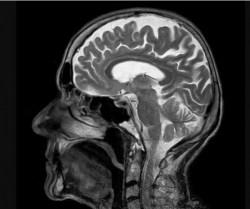

Razmere, ki prizadenejo živčni sistem – kot so možganske kapi, migrene in demenca – so prehitele bolezni srca in postale glavni vzrok za slabo zdravje po vsem svetu, je v petek pokazala velika nova analiza.

Več kot 3,4 milijarde ljudi – 43 odstotkov svetovnega prebivalstva – bo leta 2021 doživelo nevrološko bolezen, kar je veliko več, kot se je domno doslej, je pokazala analiza.

Vodilni avtor študije Jaimie Steinmetz iz IHME je dejal, da rezultati kažejo, da so bolezni živčnega sistema zdaj "glavni svetovni vzrok za celotno breme bolezni".

Raziskovalci so preuči, kako 37 različnih nevroloških stanj vpliva na slabo zdravje, invalidnost in prezgodnjo smrt v 204 državah in ozemljih od leta 1990 do 2021.

Možganska kap, ki je prej veljala za bolezen srca, je bila daleč najhujše analizirano nevrološko stanje, kar je povzročilo izgubo 160 milijonov let zdravega življenja.

Spremljala ga je oblika poškodbe možganov, imenovana neonatalna encefalopatija, migrene, demenca, vključno z Alzheimerjevo boleznijo, poškodbe živcev zaradi sladkorne bolezni, meningitis in epilepsija.

Glede na študijo v The Lancet Neurology je leta 2021 zaradi 37 nevroloških bolezni umrlo več kot 11 milijonov ljudi.